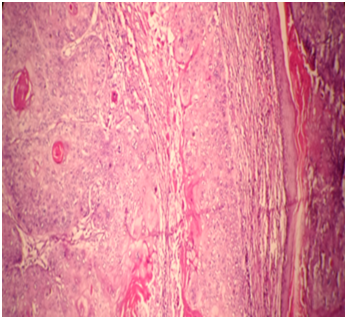

A 73year old male presented to the hospital with a solitary friable nodular mass on scalp measuring 3.5x2x1cm.She underwent local excision of this growth. Grossly, specimen consists of single piece of partly skin covered friable nodular mass 3.5x 2x1cm. Histologically, tumour shows trichilemmal keratinisation without interposed granular layer which was characterized by poor circumscription with invasion of surrounding tissue with marked nuclear atypia, hyperchromasia and atypical mitotic activity (Figure 1 & Figure 2).

Figure 2 Trichilemmal keratinisation without interposed granular layer (X40).